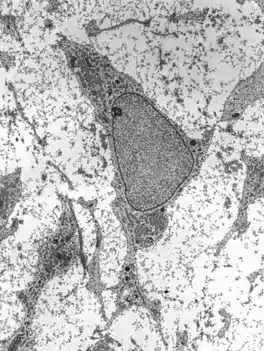

![]() Transmission electron micrograph of a mesenchymal stem cell displaying typical ultrastructural characteristics. | |

Mesenchymal stem cells are characterized morphologically by a small cell body with a few cell processes that are long and thin. The cell body contains a large, round nucleus with a prominent nucleolus, which is surrounded by finely dispersed chromatin particles, giving the nucleus a clear appearance. The remainder of the cell body contains a small amount of Golgi apparatus, rough endoplasmic reticulum, mitochondria and polyribosomes. The cells, which are long and thin, are widely dispersed and the adjacent extracellular matrix is populated by a few reticular fibrils but is devoid of the other types of collagen fibrils.[9][10] These distinctive morphological features of mesenchymal stem cells can be visualized label-free using live cell imaging.